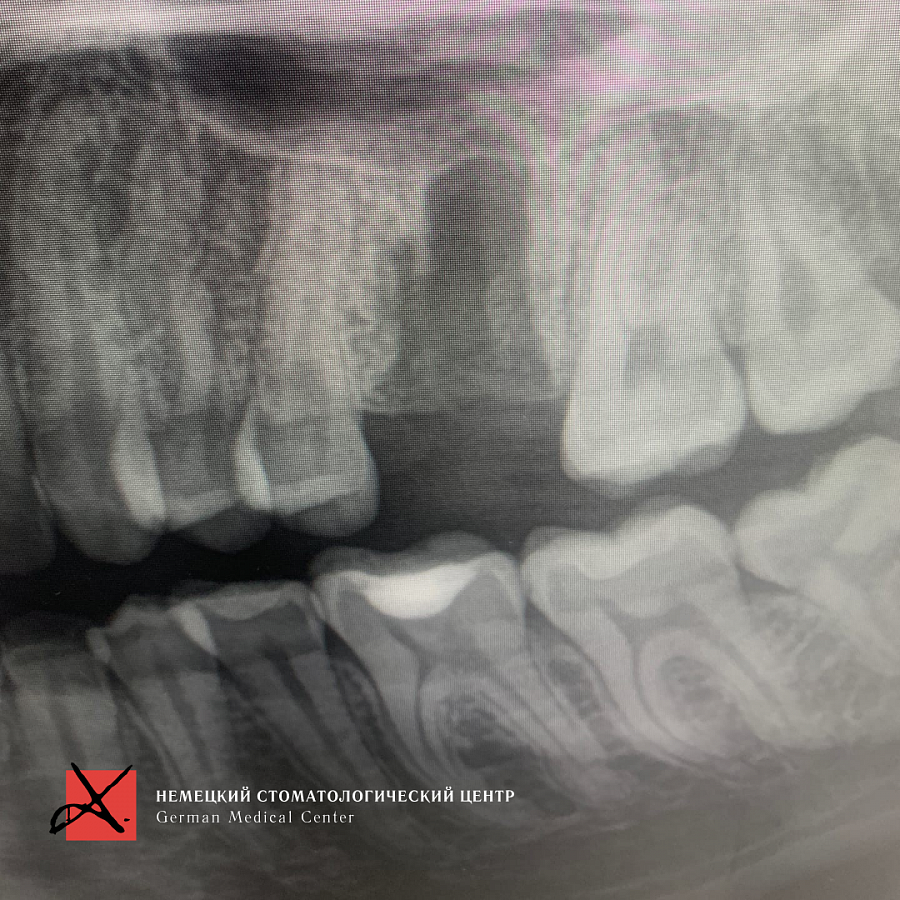

Какой диагноз поставили

На рентгеновском снимке виден костный дефект после удаления, а также перелом вестибулярной стенки.Этапы лечения